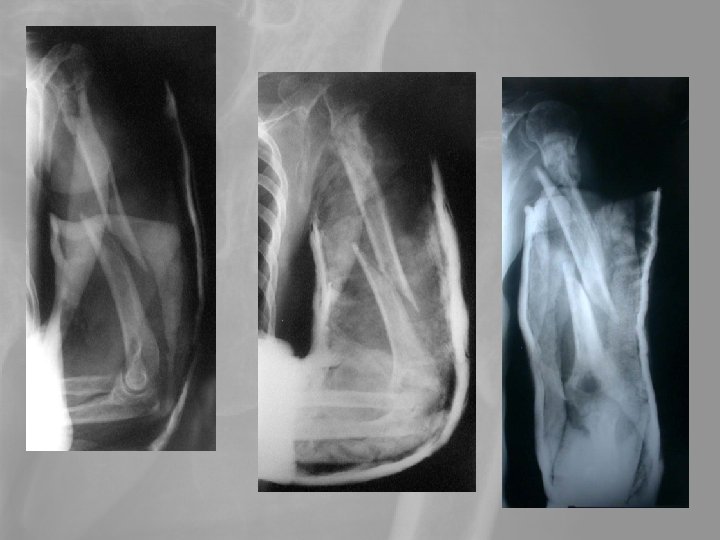

6. A proximalis humerusvég törései Idős betegek vállficam helyett a szenvedik el. A törés több darabos, porotikus. A konzervatív kezelés késői functionalis eredménye nem rosszabb, mint a műtétes kezeléseké. A vállprothesis eredményei messze elmaradnak a csípőízületi prothesisek késői funkcionalis eredményeitől.